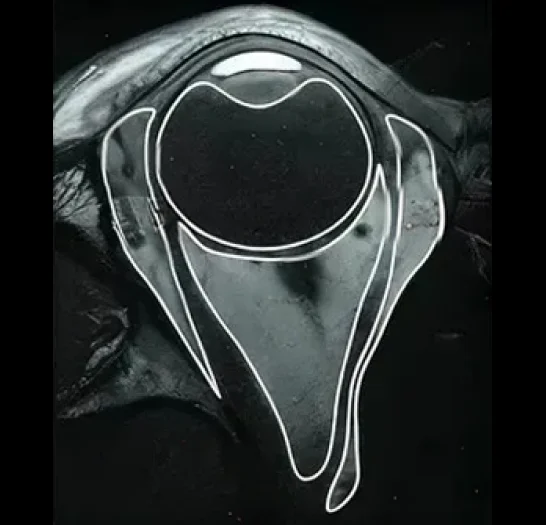

MRI Annotation & Segmentation for Ophthalmology

Pareidolia offers expert annotation of orbital and ocular MRI scans, emphasizing soft tissue contrast to delineate the optic nerve, ocular muscles, lacrimal gland, and orbital fat. We label pathologies such as optic neuritis, tumors, vascular malformations, and inflammatory processes.